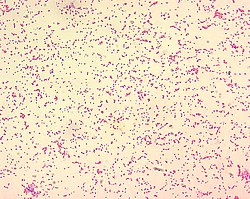

Brucella sp.

Genus: Brucella